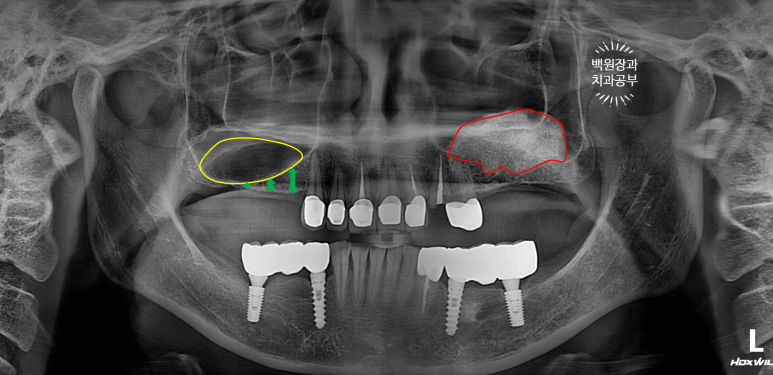

보시면 주황색 화살표로 표시된 곳이 바로 부러진 송곳니가 있는 곳..

그리고 특이하게도 왼쪽 어금니 부위에 임플란트는 없는데, 상악동 뼈이식은 되어있더라구요?

보시면 빨간색으로 표시된 왼쪽 어금니 부위는 오래 전 상악동 뼈이식술이 되어 있었지만,

오른쪽 어금니 부위는 상악동 뼈이식술이 되어있지 않아 '녹색 화살표' 만큼의 뼈밖에 없기에... (화살표를 그려내기도 힘들구만요) 상악동 뼈이식술을 미리 해야하는 상황이었습니다.

노란색으로 표시된 오른쪽 어금니 부위에 상악동 뼈이식술을 해둔다.

빨간색으로 표시된 왼쪽 어금니 부위에 임플란트를 심는다.